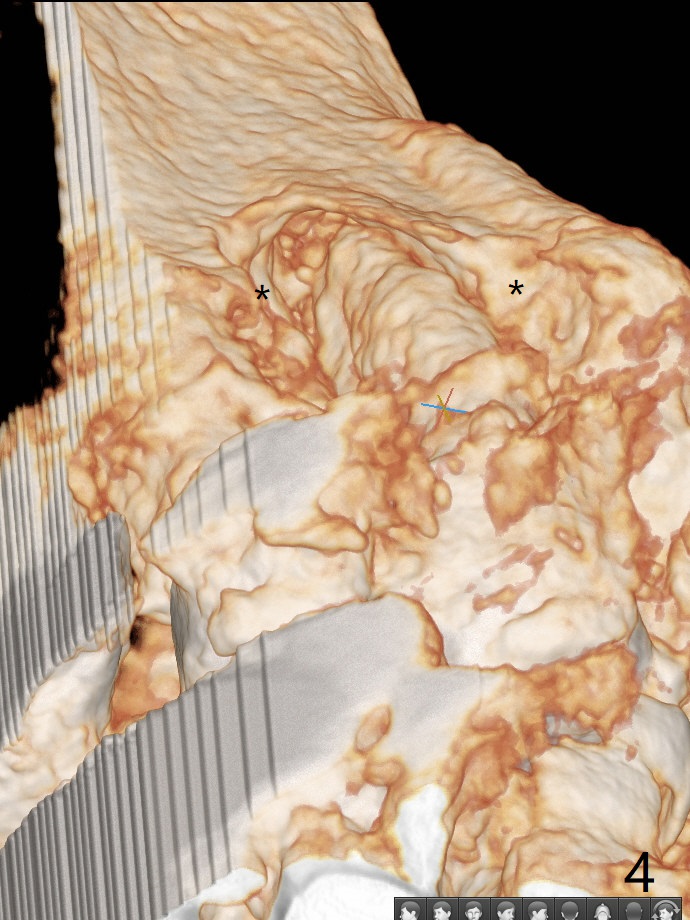

A 90-year-old man (bruxer) has porcelain fracture at #4. PA happens to reveal large PARL at #5 (Fig.1). CT taken a year ago shows missing buccal canal (Fig.2). Bone loss seems to be extensive (Fig.3,4 (root fracture?)). Access to the canal through PFM fails; the crown has to be removed (Fig.5). Fortunately the buccal canal is found and negotiable.